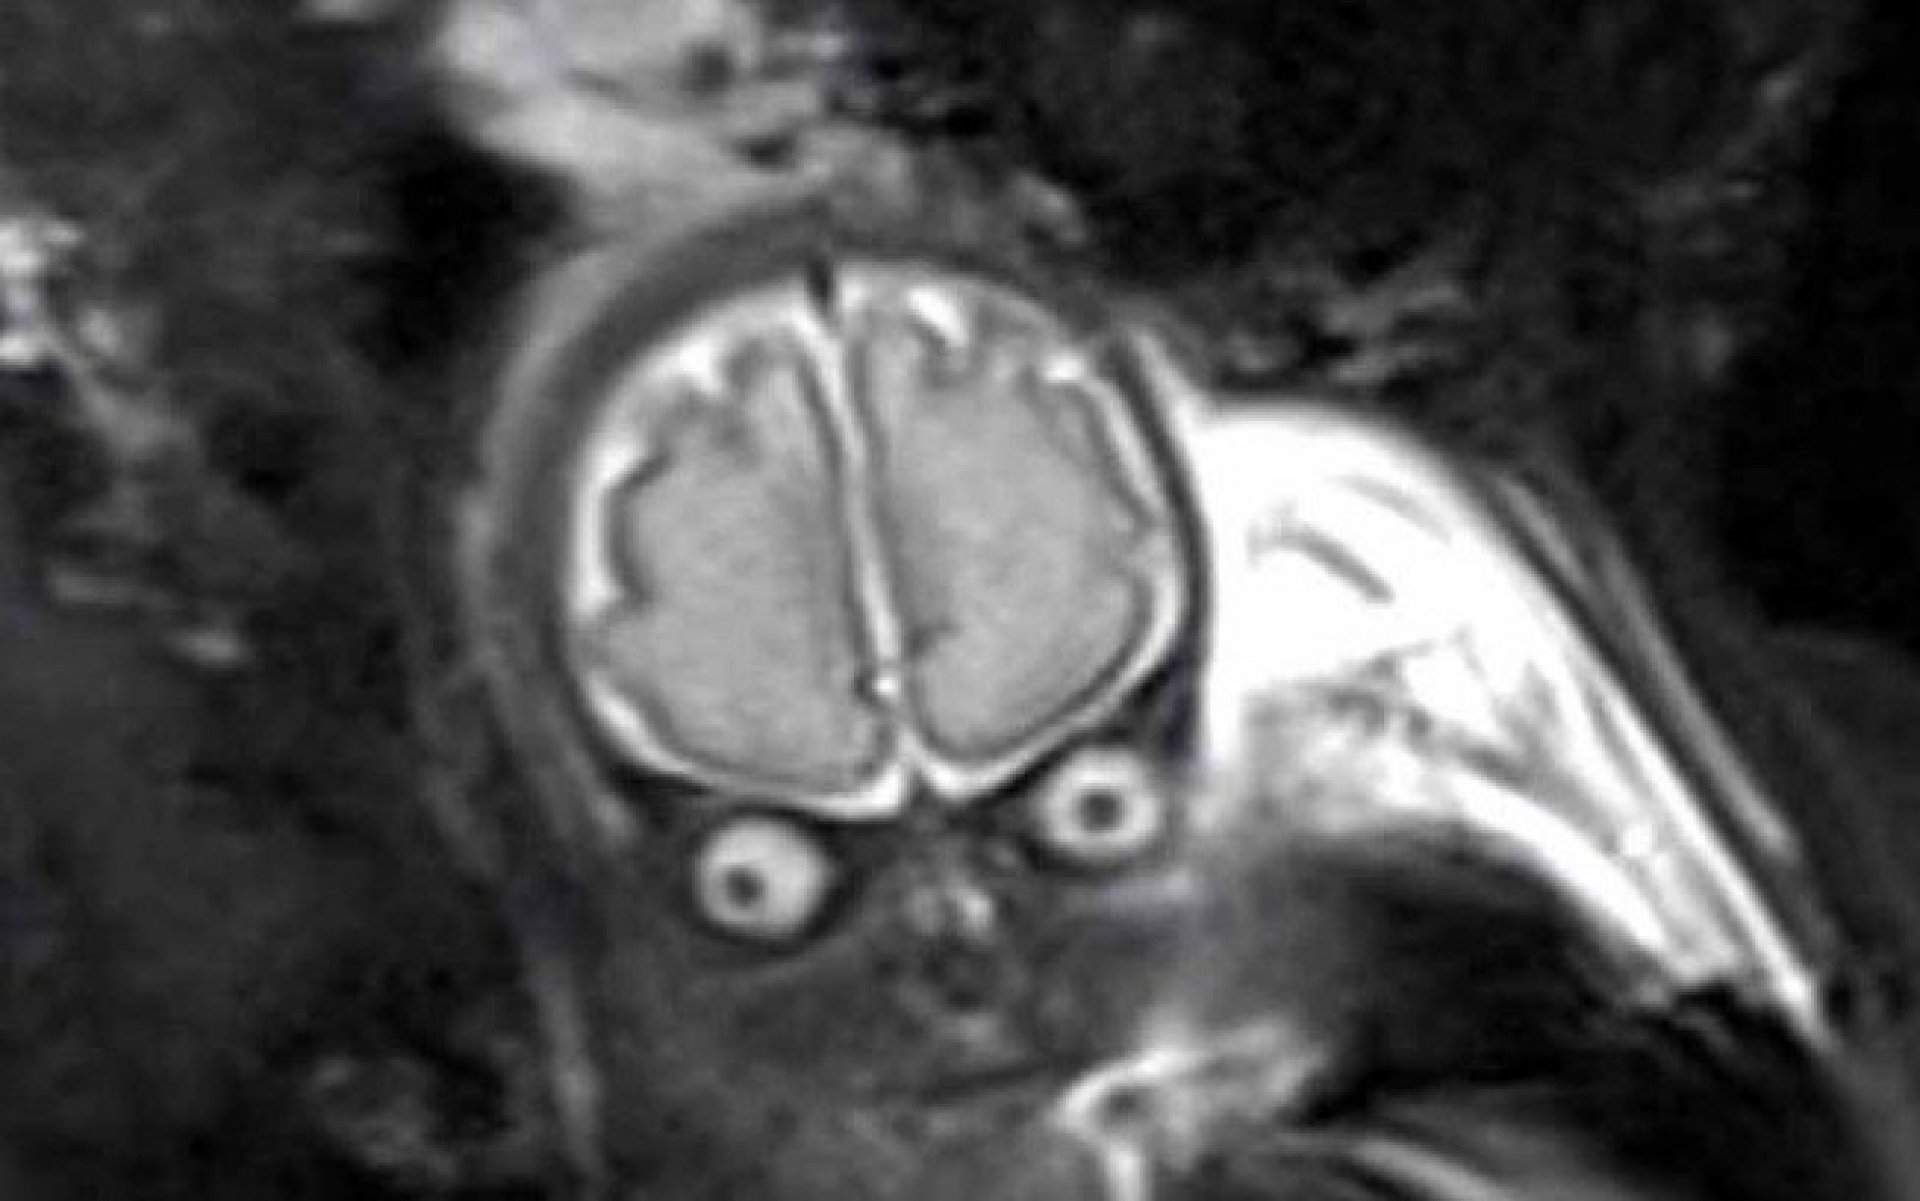

Ao identificarem uma quantidade estranha de líquido no cérebro do bebê Lucas, médicos informaram aos pais que seria necessário fazer uma tomografia para saber se estava tudo bem com ele. O resultado porém, assustou os médicos e também os futuros papais. No exame, muitos acreditaram que o feto se parecia mais com um E.T.

Antes de mostrar o resultado, os médicos decidiram preparar a mãe Laura e falaram que ela não veria a criança como costuma ver em outros casos de gravidez. Segundo o canal do Youtube Inside Edition, os pais ficaram surpresos e em estado de choque, mas depois conseguiram levar numa boa e se divertiram com a situação.

Apesar do susto, os pais tiveram a notícia que realmente importava: Estava tudo bem com o pequeno Lucas. Laura e o marido disseram que ficaram aliviados e a notícia trouxe a calma que precisavam.